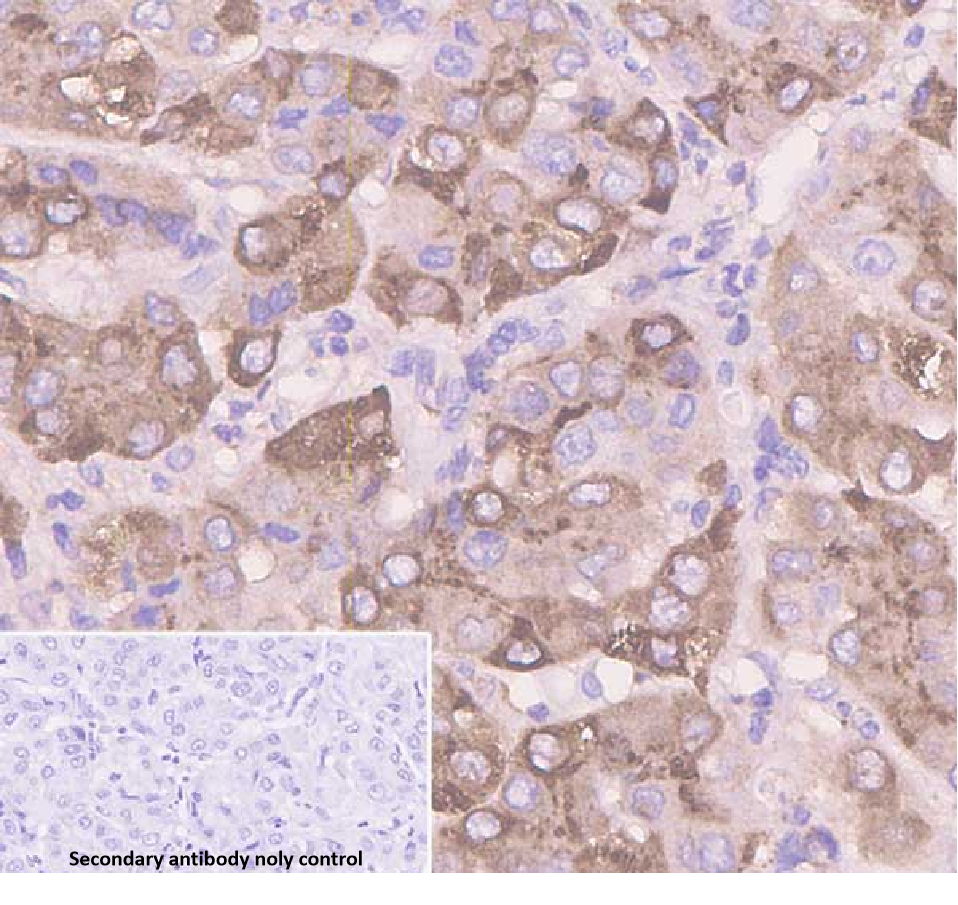

Amyloid A is an acute phase reactant protein. Abnormal deposition of amyloid A in the body can form amyloid substances. Immunohistochemical detection of amyloid A aids in the diagnosis of systemic amyloidosis, localized amyloidosis, and other diseases, and helps clarify the nature and distribution of amyloid substances. For example, the detection of amyloid A deposition in tissues such as the kidneys, heart, and liver is of great diagnostic value for amyloidosis in the corresponding organs.

Amyloid A antibody reagents can specifically bind to amyloid A molecular antigens. Immunohistochemistry kits containing amyloid A antibody reagents are suitable for the auxiliary diagnosis of secondary amyloidosis.